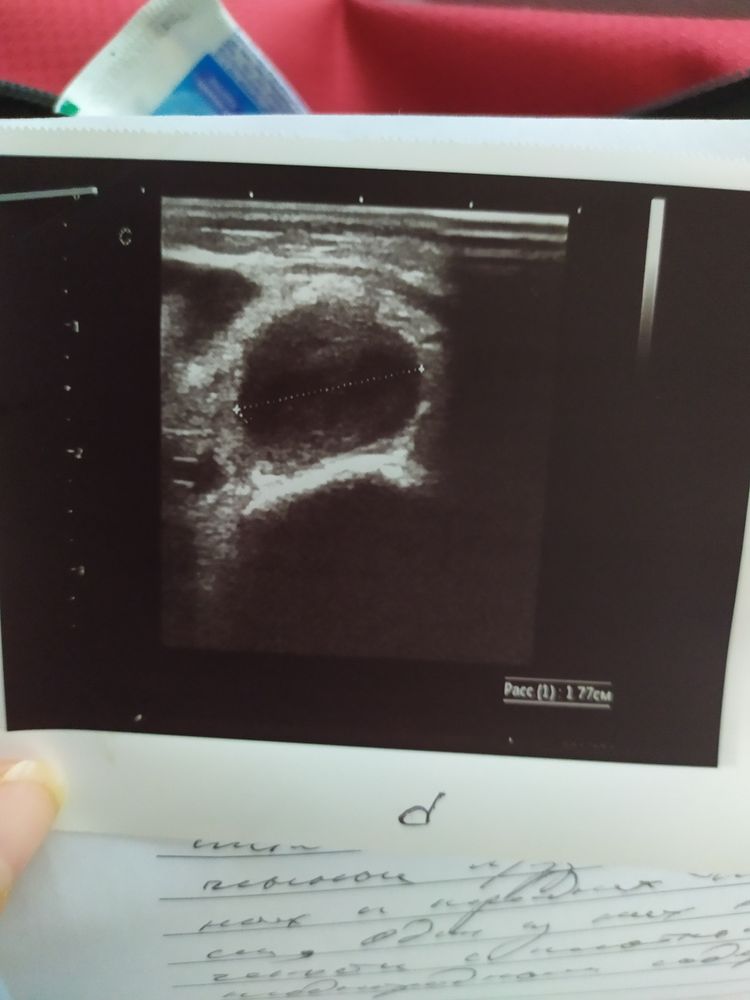

Малышке 2 недели, сегодня обнаружили на спине гнойник была корочка я немножко надавила вышло очень много гноя, не надо было конечно выдавливать но я что то сразу не сообразила . Ваткой вытерла перекись зелёнку и залепила стерильным пластырем. Врач сказала следить за температурой и Левомеколь 3раза в день.

От чего вообще могло такое вылезти и что это может быть . Фурункул??